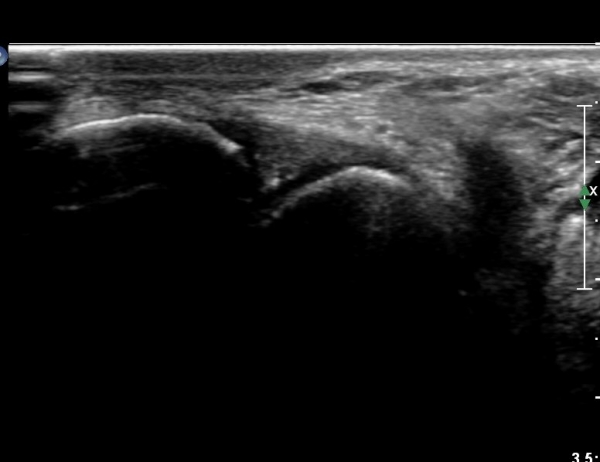

Àü°ÅºñÀδë Á¾´Ü¸é°Ë»ç¿¡¼­ Àü°Åºñ ÀδëÀÇ Àú¿¡ÄÚ ºÎÁ¶À» º¸ÀÓ(»çÁø 2).